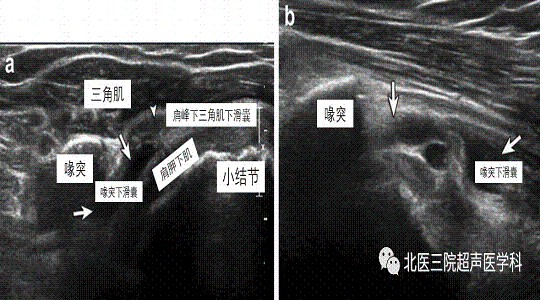

病例7--79岁女性,喙突下滑囊炎。肩关节前方横切及纵切面显示喙突下滑囊内积液(白箭),向喙突深方延伸,位于肩胛下肌腱浅方。